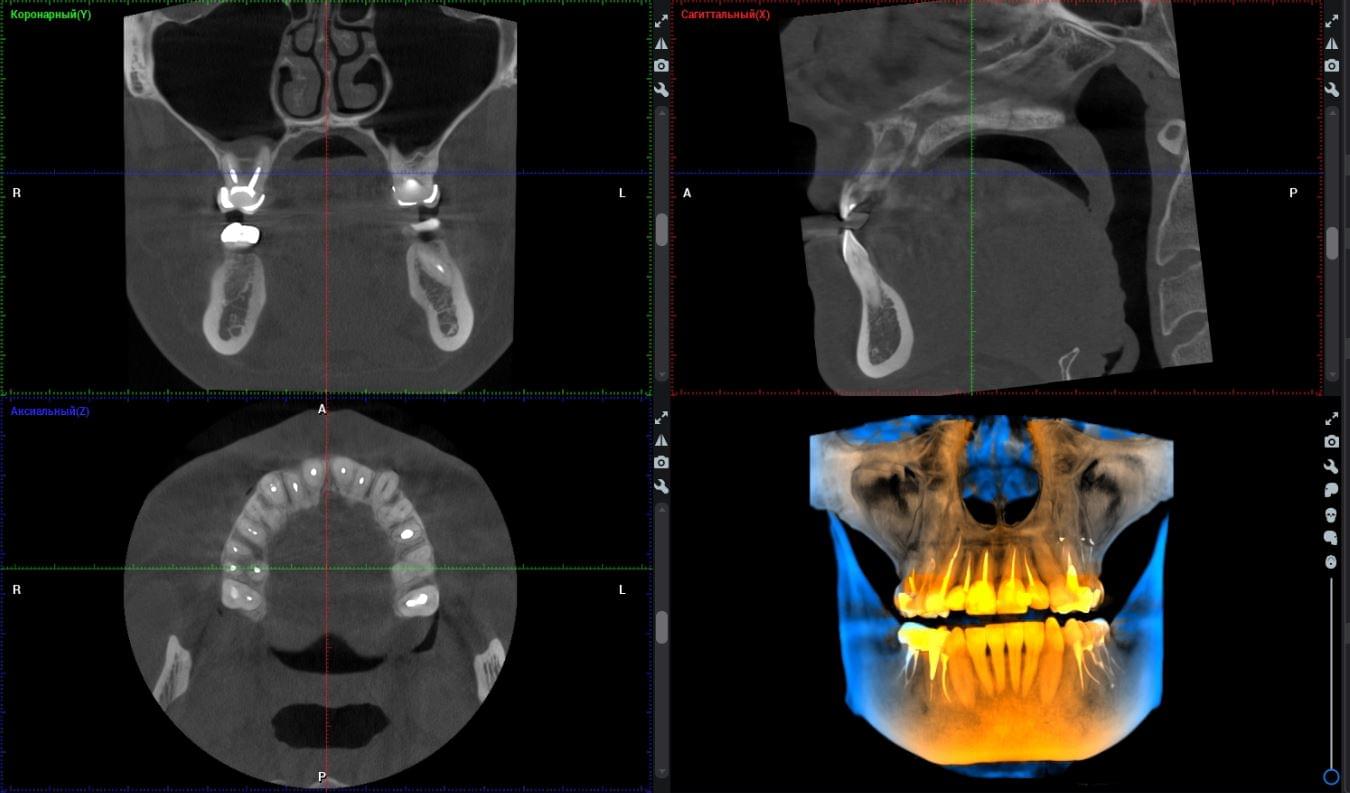

Головний недолік 2D-рентгену — це площинне зображення. Зуби, корені, щільна кістка та гайморові пазухи накладаються один на одного, створюючи «візуальний шум».

Візуальне порівняння (Кейс одного пацієнта)

Коли коріння «ховає сюрпризи» - Корені зубів часто мають складну кривизну, гачкоподібні закручення або розгалуження, які на звичайному 2D-знімку накладаються один на одного, створюючи ілюзію прямого каналу. На плоскій картинці неможливо побачити реальний об'єм та напрямок вигину, що критично важливо при видаленні «зубів мудрості» або ендодонтичному лікуванні. КТ MyRay дає змогу лікарю заздалегідь побачити 3D-геометрію кожного кореня, оцінити його близькість до нижньощелепного нерва чи гайморової пазухи та підібрати правильну тактику роботи. Це мінімізує ризики поломки інструменту в каналі або травмування сусідніх структур, перетворюючи складну хірургію на прогнозовану процедуру.

При плануванні імплантації лікарю важливо знати дві речі: об'єм кістки та точне розташування нервів.

КТ дозволяє провести віртуальну операцію: встановити імплант у програмі, виключивши будь-які ризики травмування пацієнта.

Часто причиною зубного болю є гайморит, і навпаки — причиною запалення пазух є хворий зуб. На звичайному знімку пазуха виглядає як темна пляма. На КТ ми бачимо стан слизової, наявність кіст або сторонніх тіл (наприклад, залишків пломбувального матеріалу), що критично важливо для правильного діагнозу.